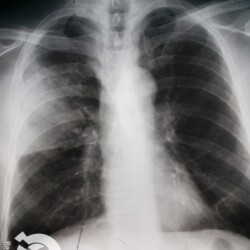

Os agentes etiológicos infecciosos são variados (bactérias, vírus, fungos, parasitas…), mas o que ocorre nos pulmões durante uma infecção por qualquer tipo de agente é a substituição do ar alveolar por secreção (pus, muco, eventualmente sangue ou necrose…) e com isso a manifestação radiográfica vai ser a mesma já que todas estas secreções apresentam a mesma densidade radiográfica: partes moles.

E o nome dado a esta alteração radiográfica que corresponde à substituição do ar alveolar por líquido é a consolidação alveolar.

Uma consolidação alveolar é, por definição, uma opacidade (imagem densa, branquinha) homogênea ou às vezes heterogênea (pela presença de calcificações ou cavidades), de limites mal definidos, exceto quando toca a pleura da parede ou das cissuras pulmonares. É um termo usado tanto em radiografia, como em tomografia computadorizada. Na tomografia, um outro termo é usado: vidro fosco, que é uma opacidade (branquinha mas não tanto como a consolidação), que borra o pulmão mas deixa ver os vasos de permeio (igual bigode de adolescente: dá pra ver todo o fundo).

Nós vamos mostrar aqui um pequeno apanhado de pneumonias de variados agentes, em diversos segmentos e lobos pulmonares, com extensões variadas. O objetivo é identificar o padrão radiológico de consolidação alveolar e não determinar o agente infeccioso, isso vai ser assunto para mais adiante. Aliás já antecipo que é fundamental saber localizar a lesão, porque alguns destes bichos gostam de determinados segmentos, alguns tumores também têm as suas preferências, então localização é fundamental. Se localização não fosse importante, um apartamento na beira do mar sairia o mesmo preço de um apartamento de frente pra BR-101, concordam?

Seguem alguns dos nossos casos de pneumonia para vocês treinarem os olhos e não se apavorarem nos plantões.